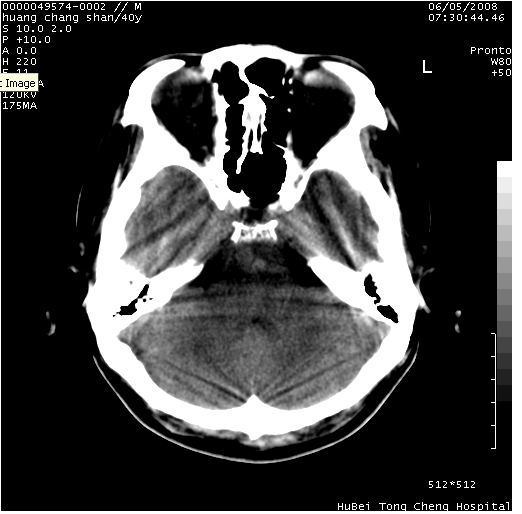

患者 m,40y。头痛,视力模糊,多饮多尿,性欲减退半年余。

行ct平扫+增强,图象如下:

鞍背无破坏和明显受压,病变明显均匀强化,边界清晰。鞍上区脑膜瘤可能性大,不除外生殖细胞瘤。

平扫病灶呈等密度,增强后强化明显,均匀一致,结合病史首先考虑:垂体瘤。脑膜瘤不支持,因为脑膜瘤平扫多为实性呈均匀高密度影像,内分泌症状多不明显,垂体内分泌素测定正常。

鞍上池肿瘤,鞍背及垂体窝形态变化不明显,病灶强化密度均匀且高度强化,考虑实性颅咽管瘤、生殖细胞瘤及脑膜瘤可能。

结合临床考虑鞍上生殖细胞瘤可能性大于脑膜瘤(增强未见脑膜围征),建议结合冠状位扫描看病灶起源及垂体窝、鞍底情况。垂体窝内未见明显软组织密度影,垂体窝未见扩大,暂不考虑垂体瘤;病灶较大,未见囊变及钙化,颅咽管瘤不支持。期待结果!